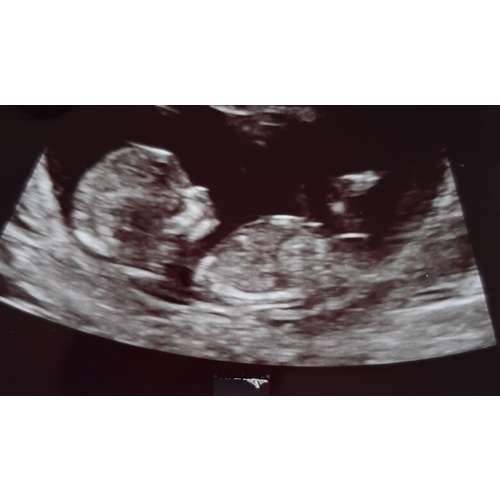

@CarolienVT1 ; ik weet niet of ik goed kijk maar ik denk een jongen馃挋

@Sassiejj3 ; ik denk een meisje 馃挆

Ik heb op je foto niks kunnen zien wat zou wijzen op een jongen. Ik snap je nieuwsgierigheid. Het is niet voor niks druk in de Nub topic 馃檲 Je had toevallig geen 3e foto toch?

Zover ik kan beoordelen is dit een meisje. Laat je het weten als je geslachtsbepaling hebt gehad? 馃槉